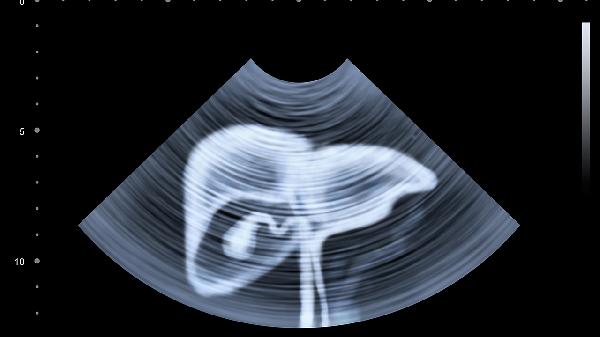

胆囊炎常因胆汁淤积或细菌感染导致,疼痛多位于右上腹,可能向右肩背部放射,急性发作时伴有发热、恶心。需进行超声检查确诊,治疗可选用消炎利胆片、熊去氧胆酸胶囊等药物,严重者需手术干预。

输尿管或肾脏结石移动时可引发右侧腹部阵发性绞痛,可能向下腹及会阴部放射,伴有血尿、尿频。确诊需依靠影像学检查,可选用排石颗粒、盐酸坦索罗辛缓释胶囊等药物促进排石,较大结石需体外冲击波治疗。